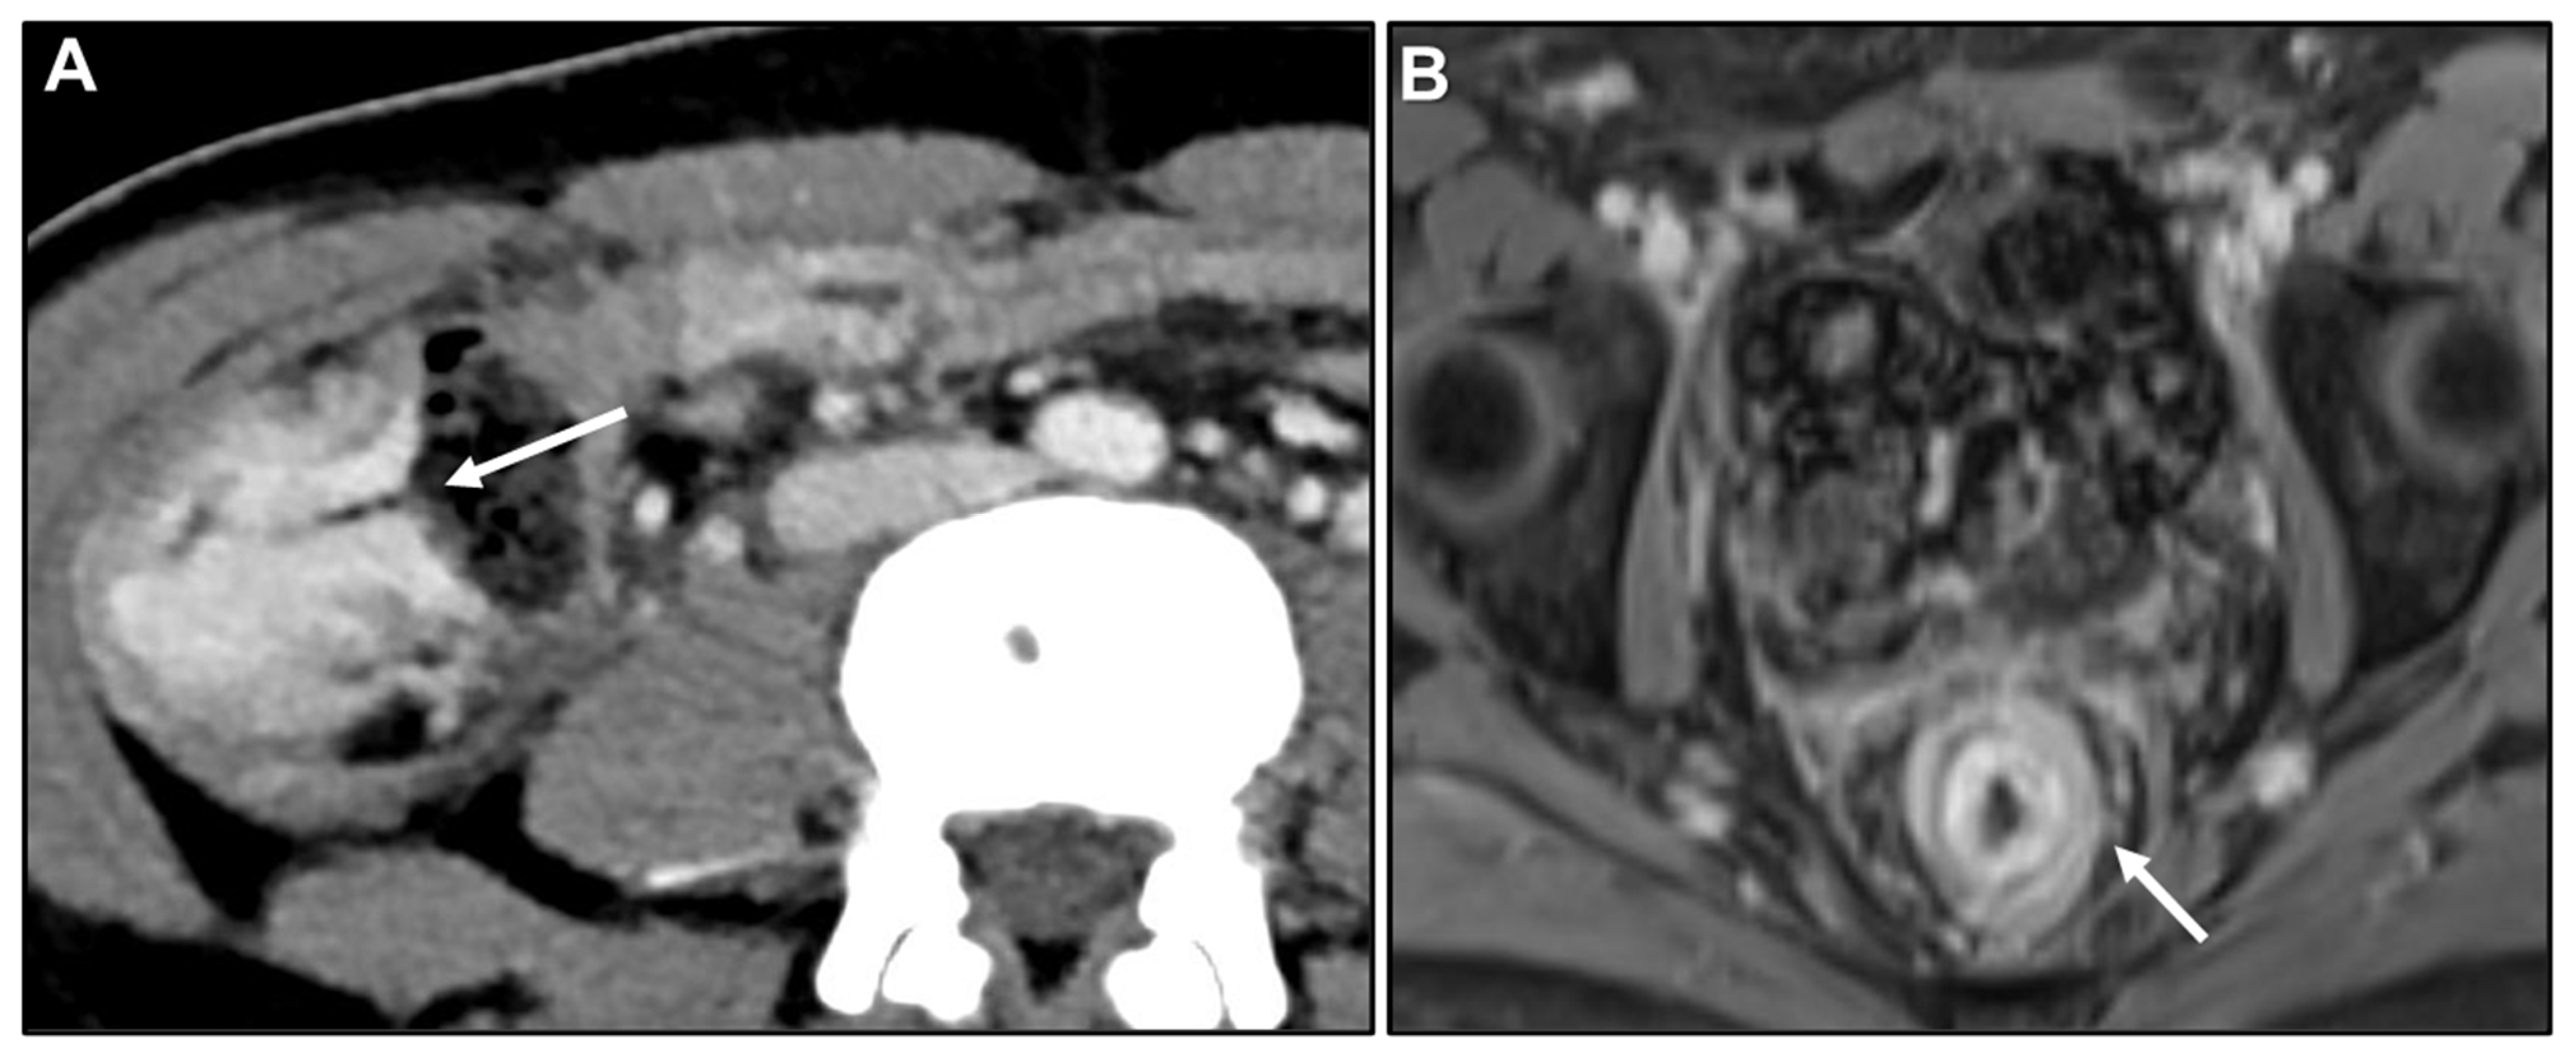

Malignant Target Sign

Homogeneous Delayed Enhancement

Concentric Ring Pattern

- Gollub, M.J.; Schwartz, M.B.; Shia, J. Scirrhous metastases to the gastrointestinal tract at CT: The malignant target sign. AJR Am. J. Roentgenol. 2009, 192, 936–940. [Google Scholar] [CrossRef][Green Version]

- Burgain, C.; Germain, A.; Bastien, C.; Orry, X.; Choné, L.; Claudon, M.; Laurent, V. Computed tomography features of gastrointestinal linitis plastica: Spectrum of findings in early and delayed phase imaging. Abdom. Radiol. 2016, 41, 1370–1377. [Google Scholar] [CrossRef]

- Lau, L.C.; Wee, B.; Wang, S.; Thian, Y.L. Metastatic breast cancer to the rectum: A case report with emphasis on MRI features. Medicine 2017, 96, e6739. [Google Scholar] [CrossRef] [PubMed]

- Rudralingam, V.; Dobson, M.J.; Pitt, M.; Stewart, D.J.; Hearn, A.; Susnerwala, S. MR imaging of linitis plastica of the rectum. AJR Am. J. Roentgenol. 2003, 181, 428–430. [Google Scholar] [CrossRef] [PubMed]